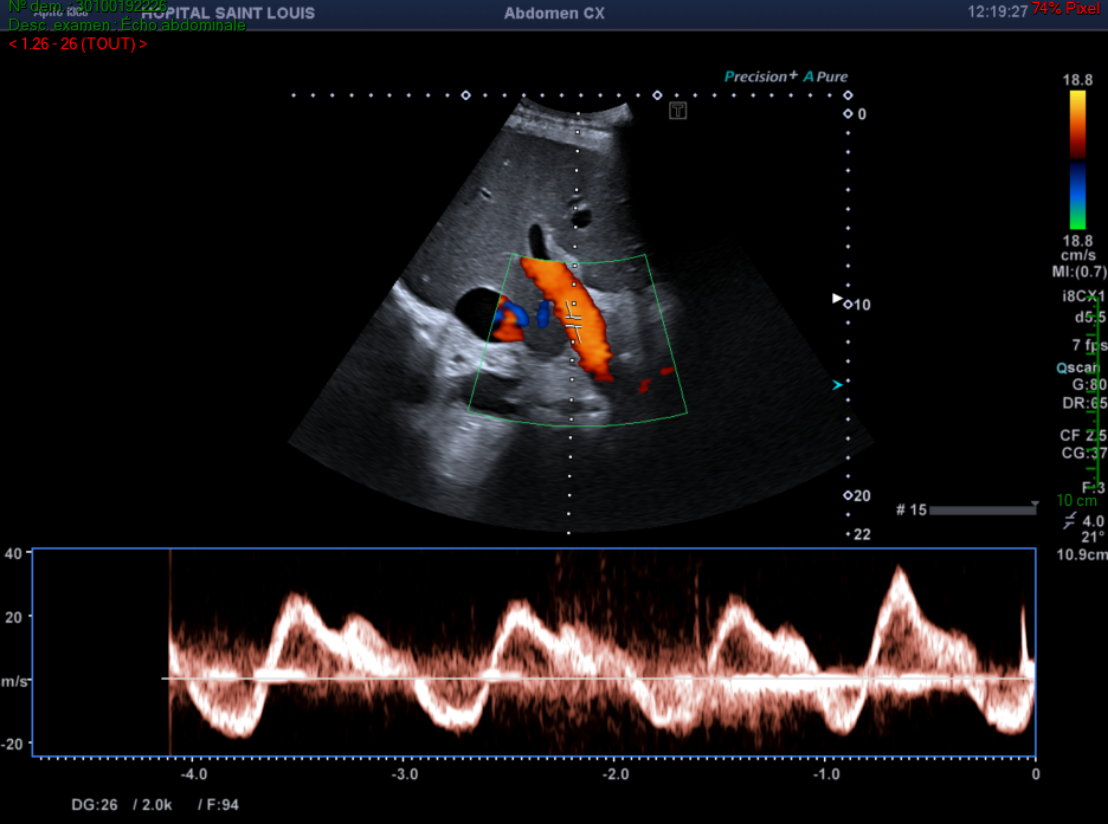

L’échographiste poursuit son exploration en étudiant la veine cave inférieure, les veines hépatiques, et en recherchant la présence d’ascite.

Il découvre alors :

Une dilatation de la veine cave inférieure.

Le calibre normal de la veine cave inférieure varie au cours du cycle respiratoire : il est maximum en inspiration bloquée (manœuvre de Valsalva) et minimum, voire collabé, en fin d'expiration. Cette cinétique est un critère important de normalité hémodynamique. Le diamètre en expiration profonde ne doit pas dépasser 25 mm

Un épanchement intra abdominal de moyenne abondance.

Une dilatation des veines hépatiques avec un diamètre mesuré à 16mm.

Le diamètre maximal d'une veine sus-hépatique mesuré avant son entrée dans la veine cave  inférieure est de 10 mm .

Une valeur plus élevée indique une dilatation, elle est typiquement retrouvée dans les insuffisances cardiaques droites.

Une perte du flux triphasique des veines hépatiques.